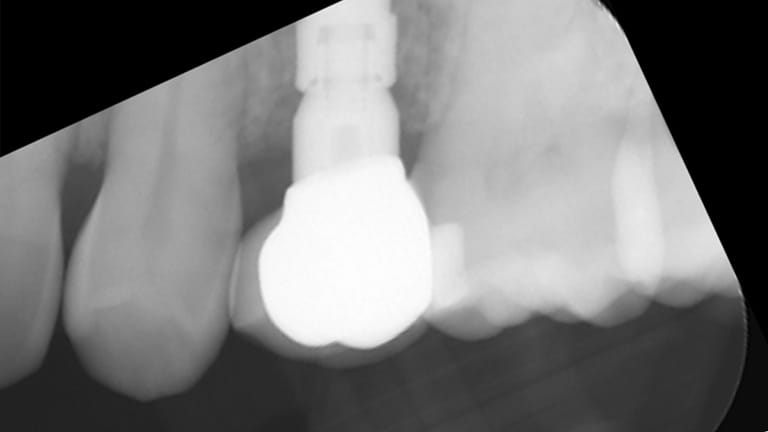

Implant (With no crown)

Implant with crown